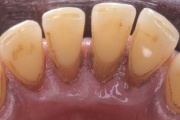

- igemepiir on taandunud (3)

- luu destruktsioon (5)

- horisontaalne luukadu (3)

- hamba kinnitussidemete kadu (3)

- igemepealne hambakivi (5)

- igemealune hambakivi (4)